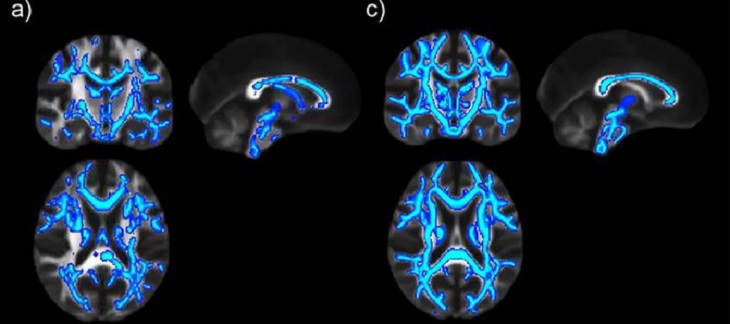

“Con el consumo de alcohol se produce un cambio generalizado en la sustancia blanca, es decir en el conjunto de fibras que comunican distintas partes del cerebro”, precisa Canals. Las alteraciones son más intensas en el cuerpo calloso –relacionado con la comunicación entre ambos hemisferios– y la fimbria –que contiene las fibras nerviosas que comunican el hipocampo, estructura fundamental para la formación de memorias–.